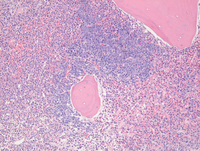

Bone core biopsy findings

Bone core biopsy shows hypercellular marrow with estimated cellularity of 90% which on higher power is notable for patchy discrete clusters of large mononuclear cells seen throughout the bone core biopsy.